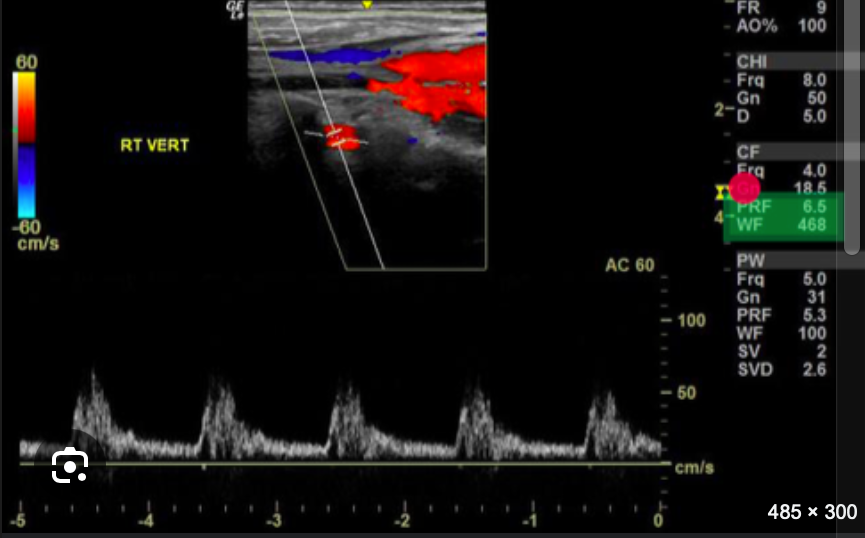

<p>What console control should be adjusted to improve the quality of the Doppler tracing?</p><p>a. increase the PW Doppler scale <br>b. adjust the placement of the Doppler cursor so it is more parallel to the blood flow<br>c. raise the baseline<br>d. reduce the wall filter setting</p>

What console control should be adjusted to improve the quality of the Doppler tracing?

a. increase the PW Doppler scale

b. adjust the placement of the Doppler cursor so it is more parallel to the blood flow

c. raise the baseline

d. reduce the wall filter setting

adjust the placement of the Doppler cursor so it is more parallel to the blood flow